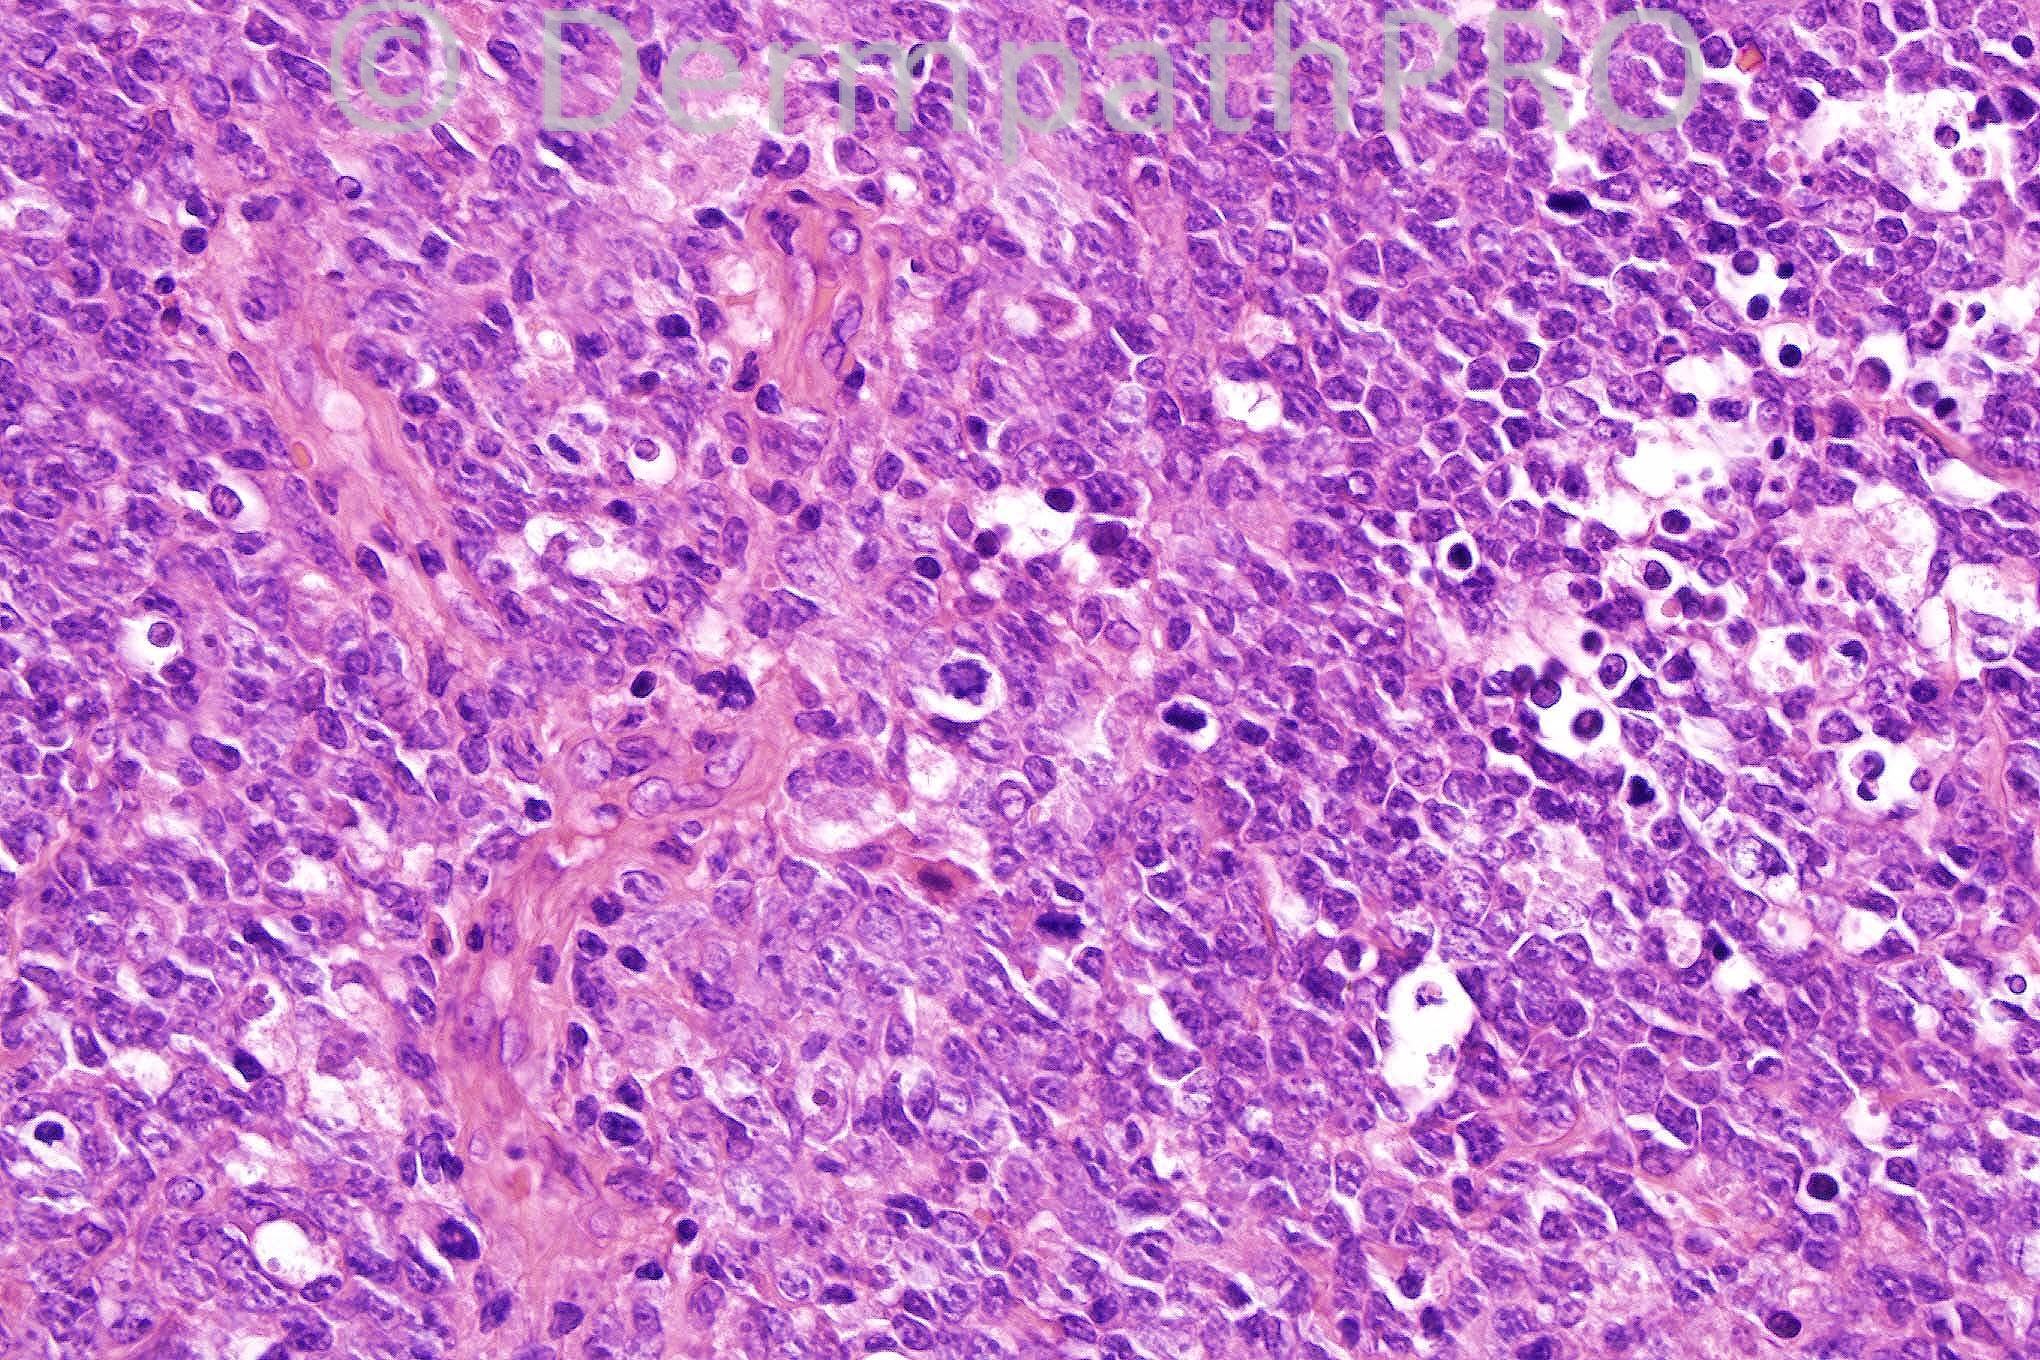

Female 73 years, previous tumour on lower limb, recurrence after three years.